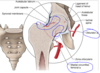

Retinacular Arteries

- arising from medial and lateral femoral circumflex arteries are the main supply to the hip joint

- Retinacular arteries from the medial circumflex femoral aa are most abundant bringing more blood to the head and neck of the femur. Ascending artery off the lateral circumflex aa also gives rise to retinacular aa.

- The artery to the head of the femur from the obturator artery travels through the ligament of the head

Blood supply interrupted with fracture of neck

- these areas are subject to infarction and avascular necrosis;

- three such regions are head of femur, body of talus, & scaphoid;

- they have the common feature that a very large portion of their total surface is covered with articular cartilage through which vessels do not penetrate;

- blood supply for these bones enters through very restricted spaces, & there is limited collateral circulation;

- when principal route of the circulation to these bones is interrupted by trauma or disease, the collateral circulation is inadequate

Avascular Necrosis of Femoral Head

- Avascular necrosis (aka: aseptic necrosis, osteonecrosis) is a condition that results from poor blood supply to an area of bone causing bone death.

- Inherent poor blood supply may lead to ischemia and necrosis of bone tissue causing weakening of the bone with eventual collapse.

- Avascular necrosis can be caused by trauma and damage to the blood vessels that supply bone its oxygen.

Other risk factors for avascular necrosis:

◦ systemic steroids, sickle cell anemia, alcohol abuse, RT (radiation therapy)

- Femur at high risk b/c it is an end organ and lined with articular cartilage where arteries can not penetrate

- Arterial supply restricted to small space

- Requires a hemiarthroplasty or THR if in adult

◦But can vary depending on the severity of the degradation of the femoral head

*bone will disintegrate and collapse